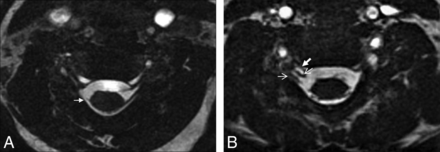

All patients had abnormal MR imaging findings on the affected side. The nerve root avulsion/retraction was seen in 43 patients in at least 1 level (n = 25) on MR imaging, and root avulsion without associated pseudomeningocele was seen in 4 patients (Fig 3A). The surgical electrophysiologic examination did not confirm the root avulsion diagnosis in 2 patients with a positive MR imaging finding, case 5 (C5) and case 49 (C5 and C6), and it revealed avulsion in 3 patients with negative MR imaging findings, cases 37 and 45 (C7, C8, and T1) and case 52 (C5). In clinical terms, there were also discrepancies between clinical findings and MR imaging in these patients (cases 5, 37, 45, 49, and 52). The pseudomeningocele without associated root avulsion was seen in 3 patients (cases 33, 39, and 42), and nerve root avulsion in the pseudomeningocele was not evaluated optimally in 3 patients (cases 5, 37, and 45) (Fig 3B). MR imaging showed 139 PSTs that usually showed signal similar to that of scalene muscles (93%, 129/139) on T1WI and higher signal (100%, 139/139) than muscles on T2WI. The locations and extensions of the PST were similar to those of US findings. The US and MR imaging showed concordance in 85% (47/55) of patients with PST (91%, 127/139) except in 8 cases (C8 [n = 4] and T1 [n = 8]) (Figs 1C and 2B). The clinical, US, and MR imaging findings were concordant in 85% of patients (47/55) with post-GI.

Case 31, in a 0.5-month-old male patient with right brachial plexus birth injury. C7 root avulsions (arrow) without associated pseudomeningocele were seen in the axial 3D-CISS image (A). Case 42, a 2-month-old female patient with right brachial plexus birth injury. The pseudomeningocele (thick arrow) without associated root avulsion (thin arrows) was seen at the C6–7 level in the axial 3D-CISS image (B).

Contrary to the post-GI, for the pre-GI, the US findings were not concordant with MR imaging and the surgical findings. This finding may be due to the technical insufficiency of US related to the artifacts caused by the transverse process of vertebrae. It has been reported that US can reveal root avulsion after traumatic BP injuries in adults.21 However, the artifacts caused by vertebrae make it difficult to see intraspinal-intraforaminal injuries despite the high-frequency probes. Thus, US has a very limited value for showing the pre-GI and full extent of the injury. However, MR myelography is superior in the assessment of pre-GI compared with US because it allows obtaining high-quality, detailed anatomic images of the intraspinal-intraforaminal contents. Although MR myelography may have limitations related to CSF flow artifacts in showing the root avulsion, it is an effective method for demonstrating not only root avulsion but also the level of the injury.6 Our study showed that MR myelography was successful in depicting the presence of the surgically proved root avulsion, and this finding was similar to those in previous studies.6,22 The diagnostic accuracy of MR imaging was 92% in our study, which is also compatible with that in previous reports.4 A pseudomeningocele can be seen with or without root avulsion, and the presence of a pseudomeningocele is highly indicative but not pathognomonic for a pre-GI.3,23 There were 3 cases with pseudomeningocele but without root avulsion (cases 33, 39, and 42) in the present cohort.